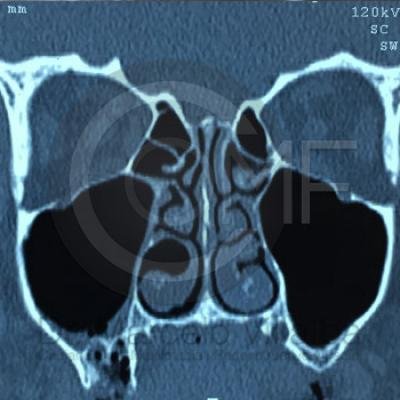

Comunicación en Seno Maxilar